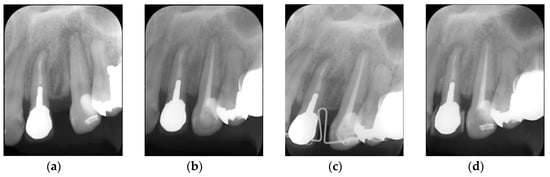

6. Clinical Performance of Bioactive Glass-Based Root Canal Sealer

7. Potential of Bioactive Glass-Based Sealer as Root Canal Filling Material Without Semisolid Core Materials